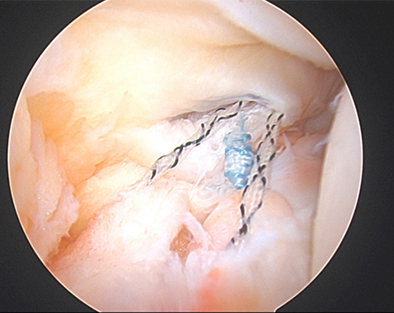

Figure 3

As such, during a diagnostic arthroscopy at the very beginning of an ACL reconstruction, is important to look closely in the back of the knee near the attachment of the posterior horn of the medial meniscus to see if there is a disruption in the capsule. If there is a tear in this capsule region, it is debatable on which ramp tears are considered stable versus unstable. Nonetheless, it is important to discuss your surgeon's approach to ramp lesions and threshold to repair them. In our practice, we repair nearly all ramp lesions identified during the diagnostic arthroscopy. In fact, Dr. Momaya’s team has published a novel anchor based technique for ramp repair. Figure 2-4 demonstrates the repaired ramp lesion in a collegiate football athlete via a lasso and suture technique.